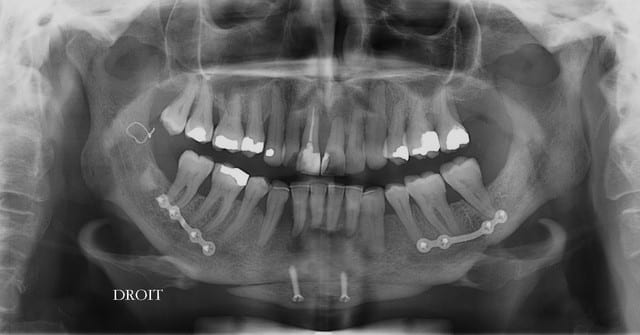

Patiente 58 ans à eu une chirurgie à visée esthétique et "fonctionnelle" adressée pour détartrage en urgence...je ne suis pas spécialiste mais je trouve que la greffe mentonnière est très bof

lésion apicale sur 42 risque de contamination sur la vis en regard..

j'ai demandé un scan en urgence.

Car se taper un traitement orthodontique avec extraction de 7 dents (4 prémolaires + 3 DDS) puis (peut-être dans un retraitement)une chir orthognathique, et se retrouver dans une situation de devoir faire un"détartrage en urgence", c'est qu'elle n'a pas bien compris l'intérêt d'entretenir tout ce dont elle a bénéficié.

Plusieurs points: les vis de 15mm x 2mm qui transfixent c'est pas top, une seule plaque, qui plus est non réglable de chaque côté, c'est encore moins top. C'est une plaque de fracture.

En mandibulaire gauche c'est quoi ce fil d'osteosynthese? Un troisième fragment? En laissant l'apex de la 48 pile sur le trait d'osteotomie, je dis chapeau.

Pour la lésion de 42, ca peut être lié à la genio. Forage hasardeux? Mais je vote plus pour une lésion endo/paro

il y a de l'os autour de 11 et 21 ?

On dirait une chirurgie des années 90 :-(

Je ne suis pas fan des extractions multiple mais là, à part les secteurs molaires, je ne suis pas sur de pouvoir sauver quelques chose(surtout mandibulaire)